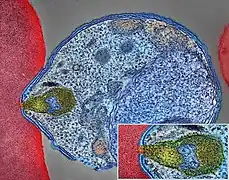

| Malaria parasite connecting to a red blood cell | |